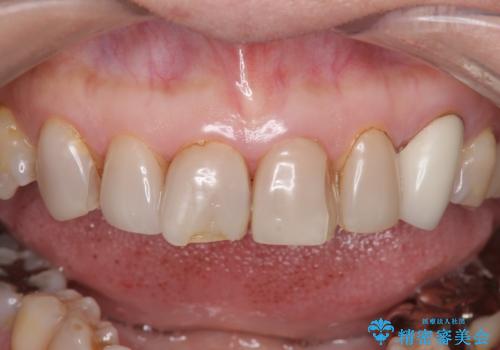

- 上下顎前歯部の見た目が気になるといらっしゃった方の症例です。

上顎は左4番から右4番までの8歯、下顎は左3番から右3番までの6歯、計14歯をオールセラミッククラウンにより補綴しました。

今回用いたオールセラミッククラウンはジルコニアフレームという白い素材の上にセラミックを盛っているため、審美性が非常に高いのが特徴です。